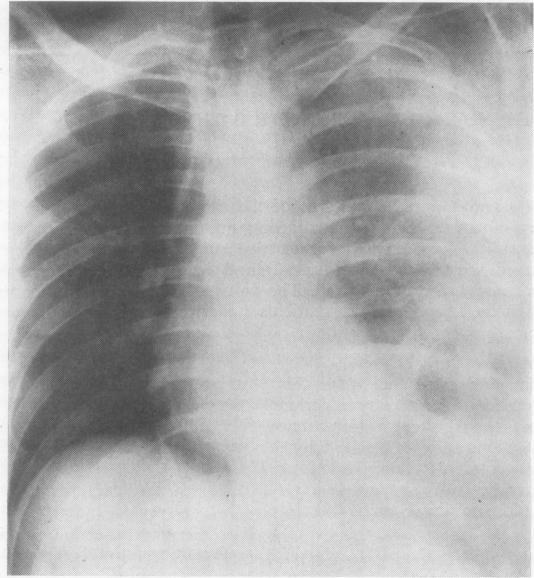

Seven patients who had traumatic ruptures of the thoracic aorta are reported. Four of these died within a few hours of admission, allowing no opportunity for diagnosis or treatment. However, three survived long enough for elective surgery to be undertaken. A diagnosis of ruptured aorta was missed in one patient (case 2), and the difficulties of diagnosing this condition, even during thoracotomy, are emphasized. The value of serial chest radiography and forward aortography is discussed. Two of these patients underwent successful aortic repair, using left atrio-femoral bypass.